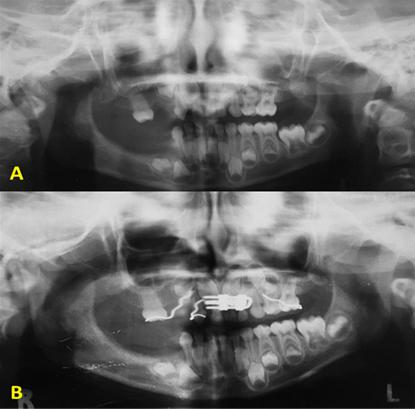

The medical history showed that given the anterior crossover, the patient underwent orthopedic treatment with a Hawley plate with expansion screw and buccal clasps for maxillary retraction (Fig. 1A and 1B). As a result, the crossover was corrected and arch perimeter was gained for the eruption of permanent teeth. In addition, in 2011, a temporary removable partial prosthesis was made to restore functionality and aesthetics. Currently, the patient seeks assistance to have her prosthesis replaced.

Fig. 1: A. (Panoramic radiography, 2007, before placing the orthopedic appliance). B. (X-ray of the orthopedic appliance with an expansion screw, posterior to the palatal disjunction stage).